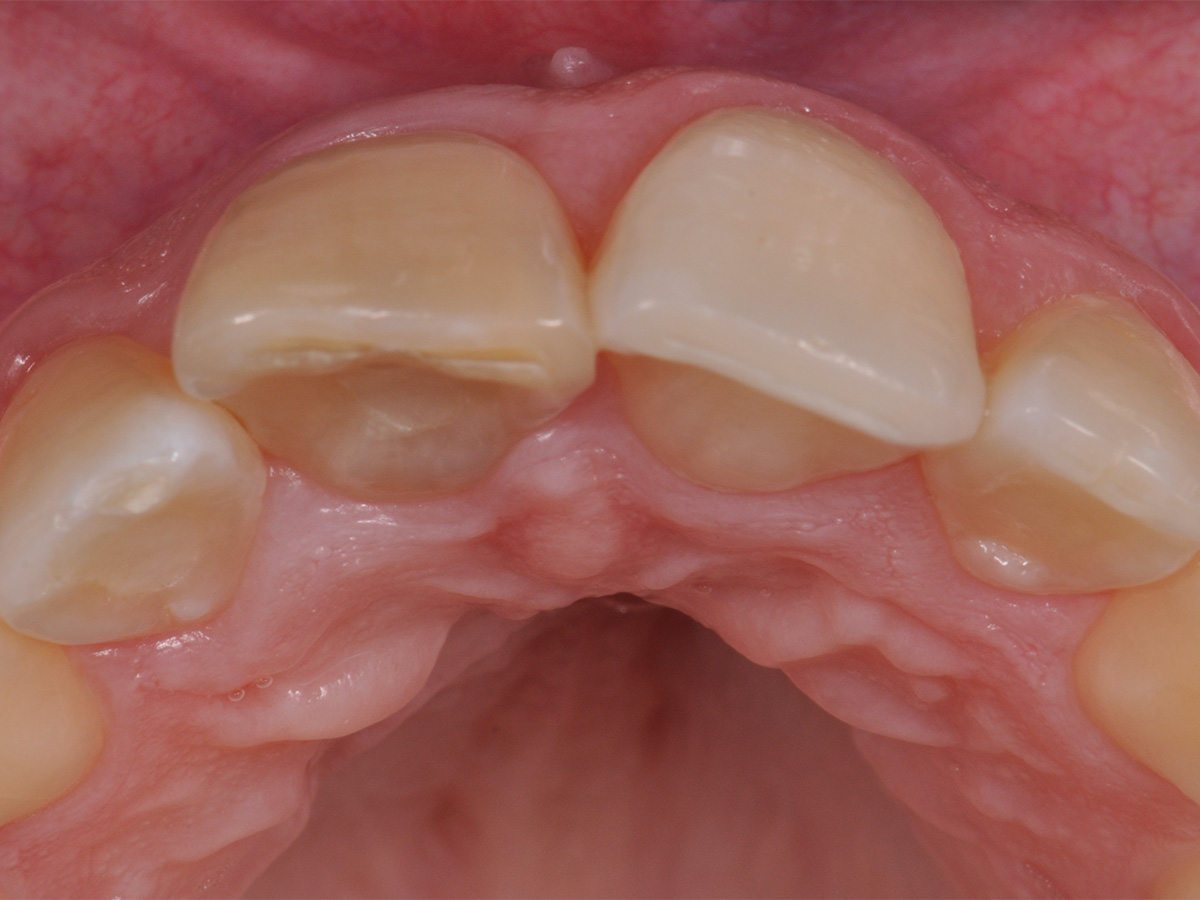

Abbildung 3

Prä-OP: OK von okklusal.

Nach einem Zahntrauma im Jugendalter mit anschließender endodontischer Versorgung stellte sich unsere 24-jährige Patientin mit seit einigen Monaten bestehendem, rezidivierendem Druckgefühl und leichten Schmerzen in regio 11 und 12 vor (Abb. 1, 2, 3). Die klinische Untersuchung ergab an Zahn 11 und 12 Lockerungsgrad 1 und, wie zu erwarten, eine negative Sensitivität. Es lag ein leichter Perkussionsschmerz vertikal wie horizontal vor. Die Krone auf Position 11 zeigte eine leichte Verfärbung im Vergleich zu den Nachbarzähnen. Ein OPG ergab eine – in ihrer Ausdehnung nicht sicher zu beurteilende – Aufhellung im Knochenbereich regio 11 und 12 (Abb. 4). Als Nebenbefund waren teilretinierte Zähne 38 und 48 sowie ein vollständig retinierter Zahn 28 als Mikroform nachzuweisen. Ein zusätzlich durchgeführtes DVT zeigte eine große zystische Formation unter Einschluss der Wurzeln 11 und 12, die vom Canalis nasopalatinus bis mesial 13 mit einer kleineren Perforation zum Nasenboden und größeren Perforationen nach vestibulär und palatinal reichte (Abb. 5, 6, 7).